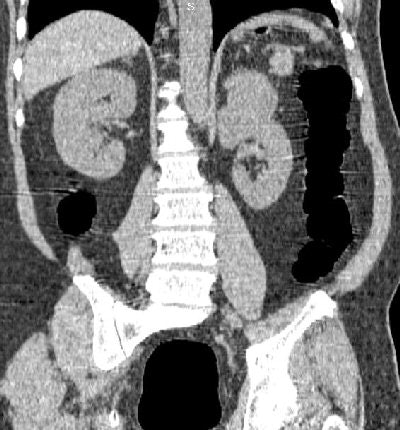

The mean age of patients with findings was 58.2 years, the same as the age of the cohort overall. Significant findings included three renal cell carcinomas, three lymphomas, and one bronchial adenocarcinoma, she said. (The lower lung is included in VC imaging to capture the entire colon.)

| A renal cell carcinoma (above) and a lung adenocarcinoma (below) are detected at screening VC of asymptomatic subjects. All images courtesy of Dr. Perry Pickhardt. |

There were eight previously unknown arterial aneurysms, and seven patients with gallbladder or kidney disease. Twelve arterial aneurysms, including eight aortic aneurysms, were found. Obstructing urolithiasis was seen in three patients, obstructing urolithiasis in three, porcelain gallbladder in two, and one case of autosomal dominant polycystic kidney disease.